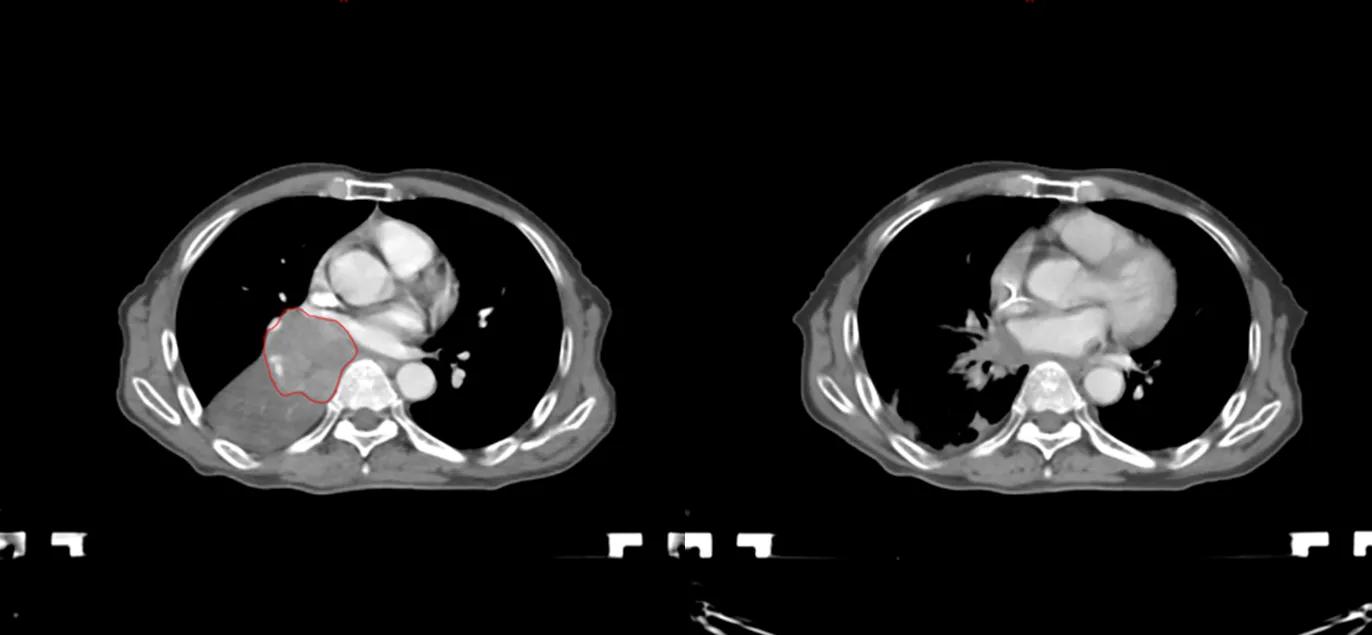

与这些名人患肺癌的同时,笔者治好了至少5位晚期肺癌病人(见下图CT片显示的肿瘤)。笔者病人有咳嗽,咯血,胸痛,胸闷,气急等症状,病人家属知道亲人是晚期肺癌,没有抱多大希望,治疗的目的只是想减轻一些症状,延长生命。经过笔者的精心治疗,2例现已活了5年多,2例已活过3年多,1例已活过2年多。治疗时年龄最大有82岁,最小年龄51岁,他们现在都生活得很好,甚至一个来自江西农村的病人一直在田地里干重体力农活。

治疗前后CT对比,红色为肿瘤(左),治疗后肿瘤消失(右)